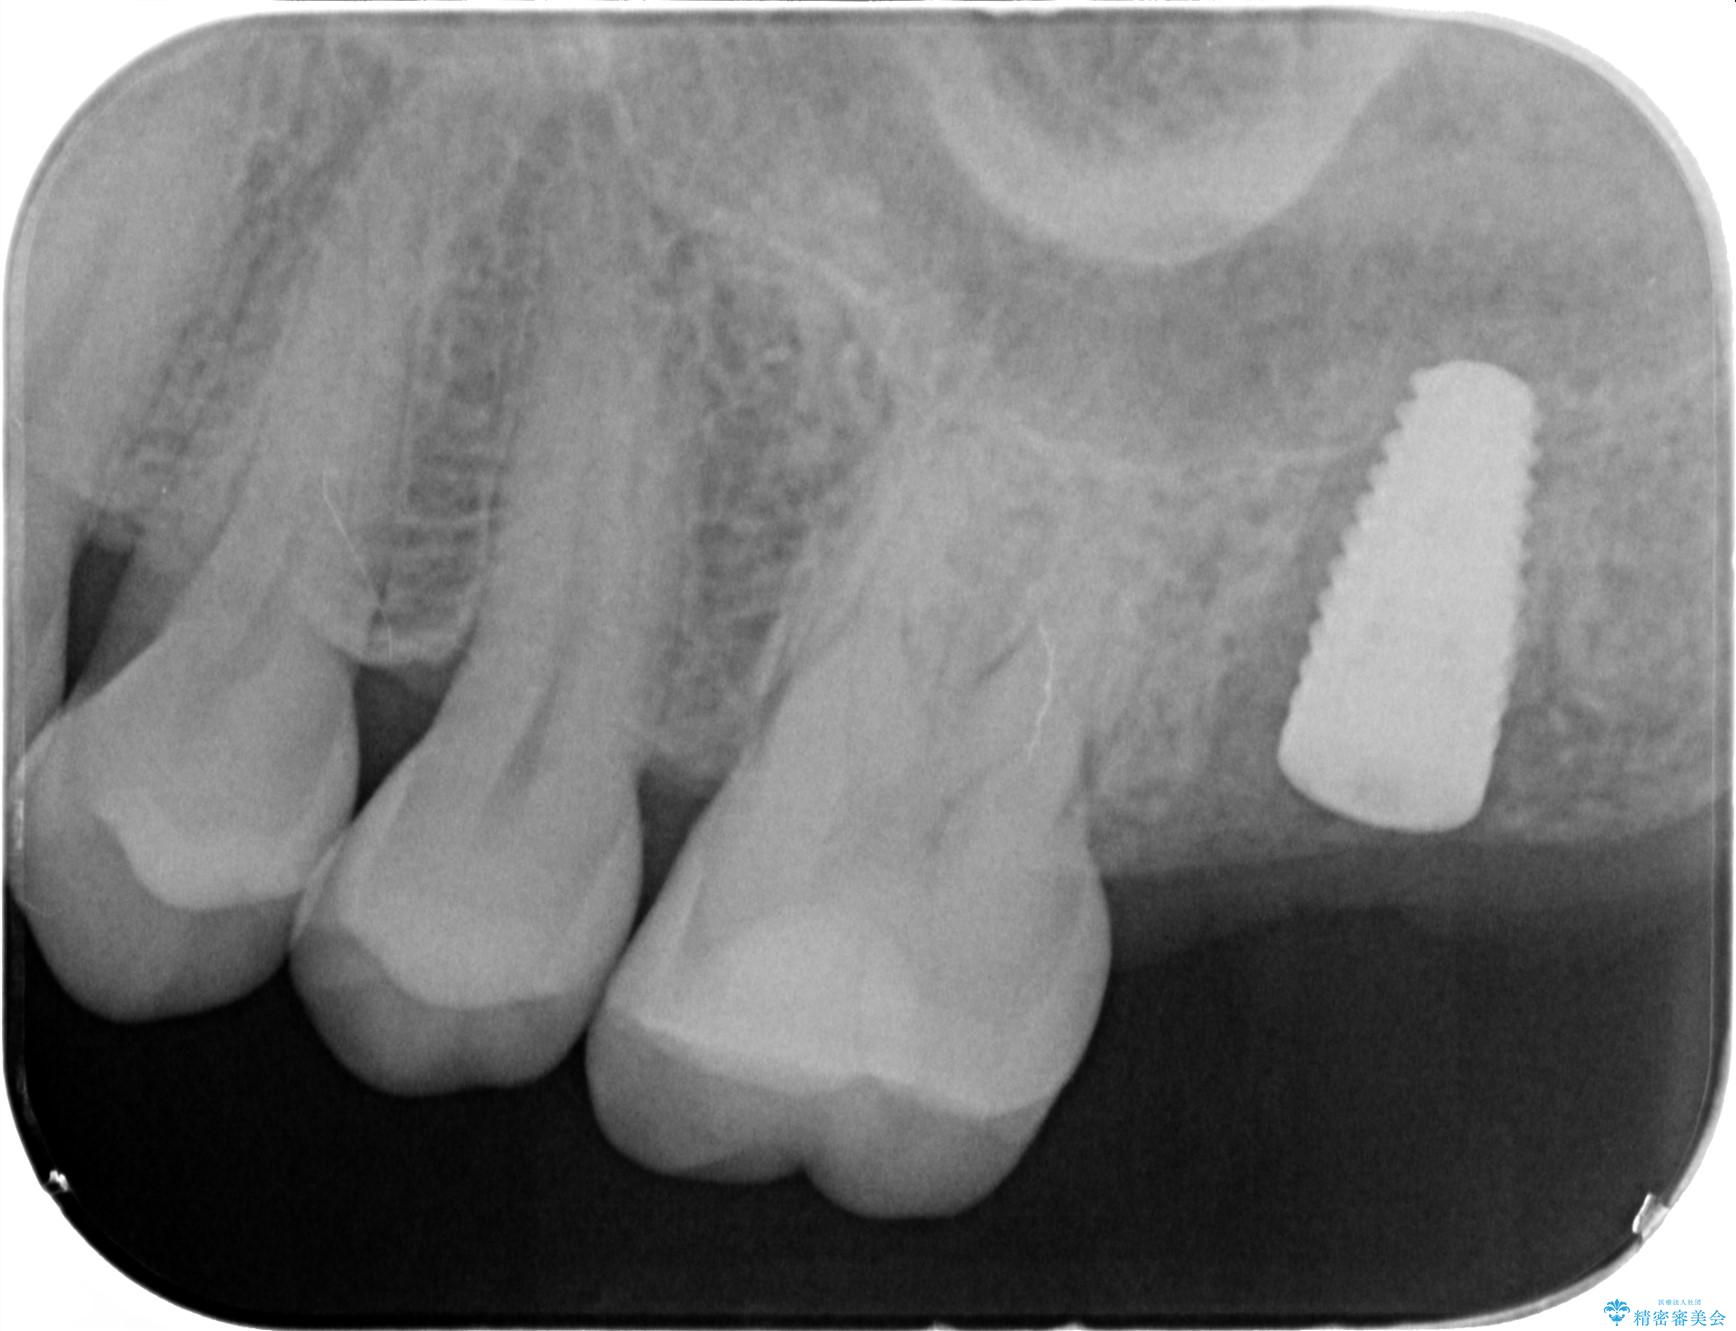

精査した結果、上顎奥歯は歯が割れてしまっており、根管治療ではなく抜歯の対象でした。

歯の抜去後、しっかりと咬合機能を回復するためインプラントを用いた治療を行っていきます。

治療中

【噛むと歯が疼く】歯牙破折からのインプラント治療 治療中画像 【噛むと歯が疼く】歯牙破折からのインプラント治療 治療中画像 【噛むと歯が疼く】歯牙破折からのインプラント治療 治療中画像 【噛むと歯が疼く】歯牙破折からのインプラント治療 治療中画像